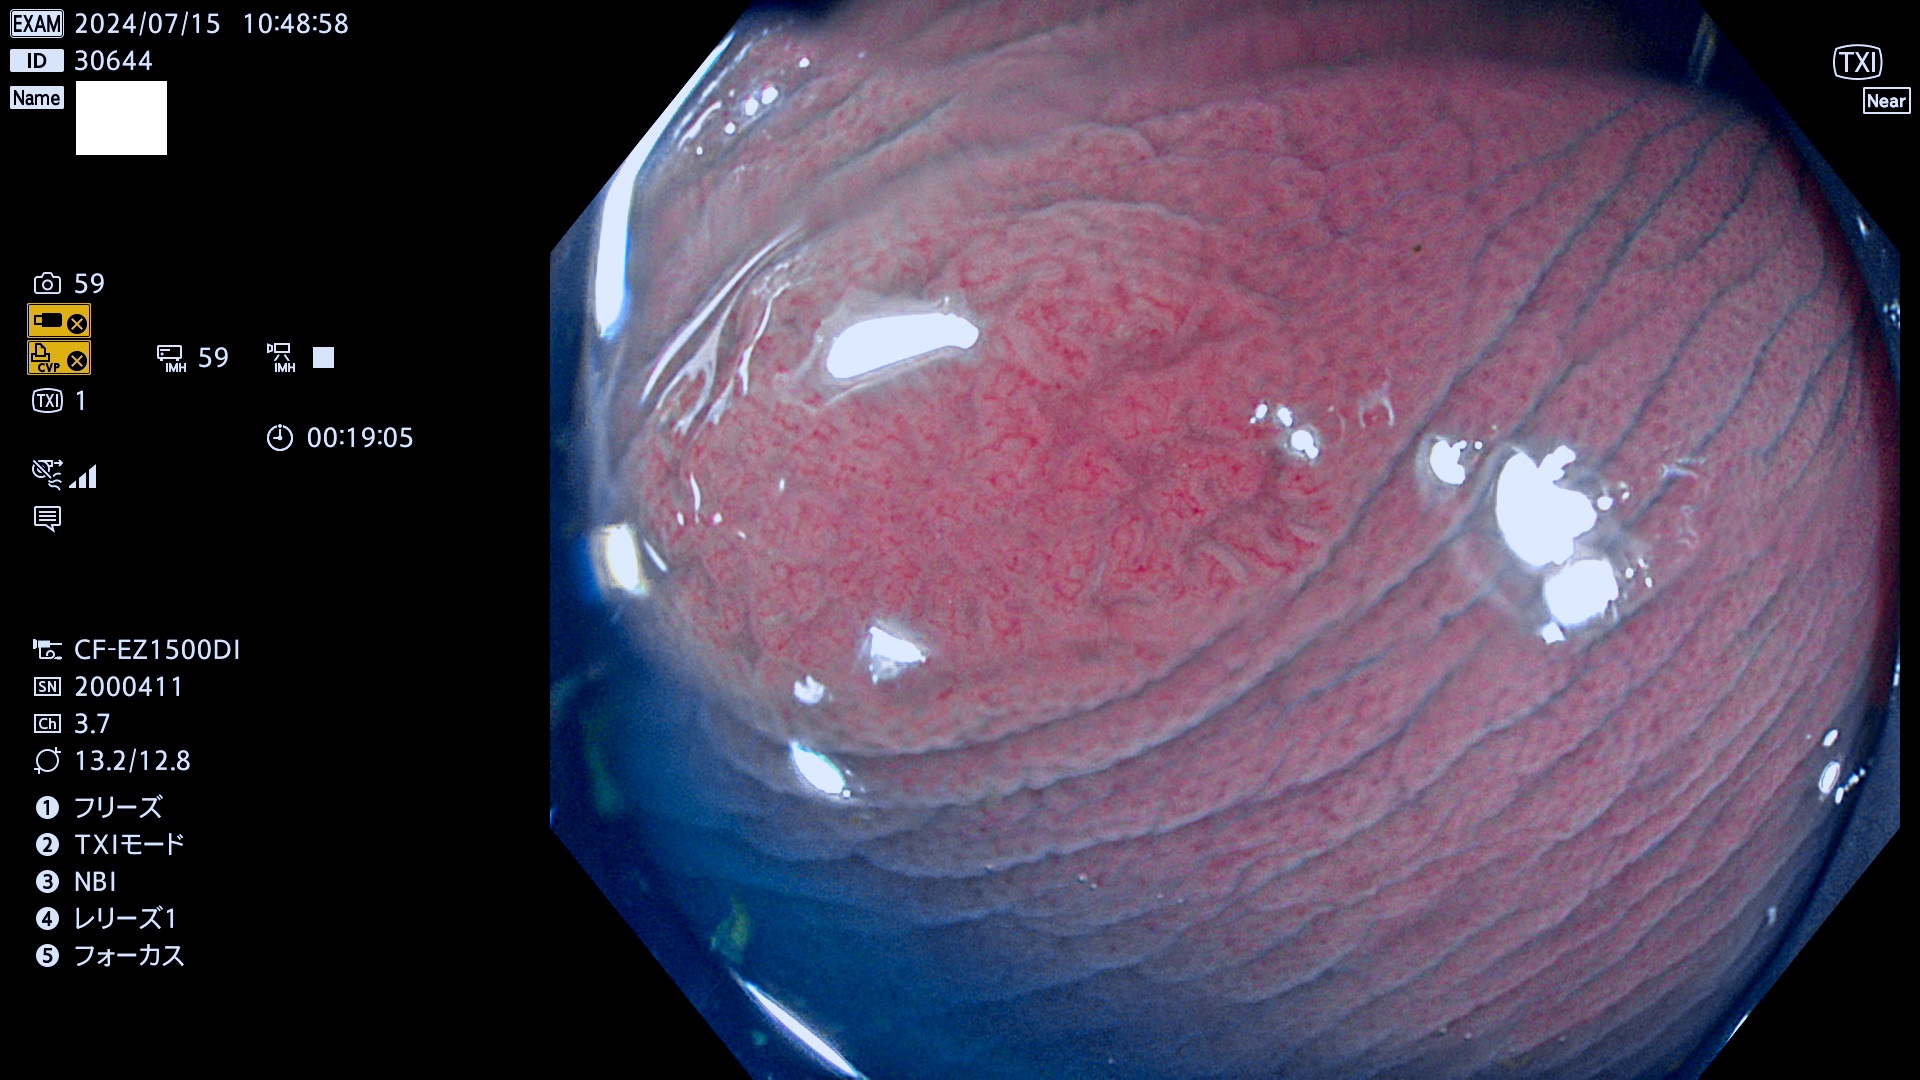

今週のUb、Uc型腺腫

完全に平坦な物をUb、陥凹している物をUcと呼びます。最も発見が難しく危険な病変です。

毎週の検査(木・金・土・日)に発見されたUb、Uc型・腺腫を、その週の日曜の夜にUPし1週間、提示します。

抽出の対象期間 2024年7月4日〜7月14の8日間(50件の検査)4件 (4/50=8%)